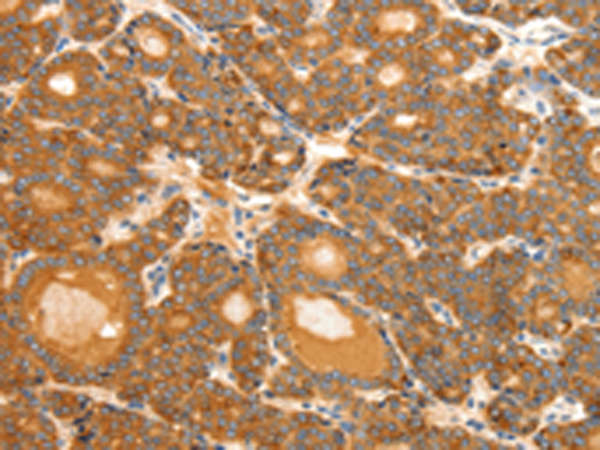

ELISA, IHC |

IHC positive control: |

Human thyroid cancer and Human ovarian cancer |

IHC Recommend dilution: |

50-200 |